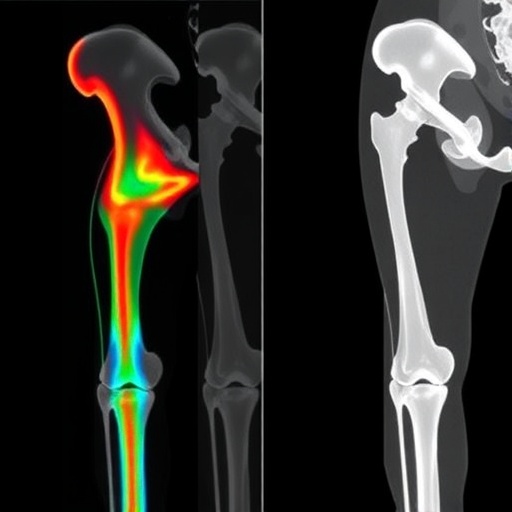

Radiomics—the extraction of high-dimensional quantitative features from medical images—has been gaining traction as a powerful tool to decode the complex biological response to cancer therapy. Central to this study is the application of radiomic analysis specifically focused on the femoral head and neck bones in patients treated with HT, a form of intensity-modulated radiation therapy renowned for its precision and conformal dose delivery. By systematically evaluating radiomic features (RFs) over the course of treatment, the research addresses critical gaps in understanding how bone tissue structurally adapts or deteriorates in response to radiation.

The investigative team conducted their analysis on a cohort of 20 male patients, equally divided between prostate cancer (PCa) and rectal cancer (RCa). MVCT imaging datasets were acquired at three key time points—baseline, midpoint, and treatment conclusion—allowing for longitudinal tracking of radiomic feature changes. The femoral regions of interest were meticulously segmented, ensuring accurate capture of tissue morphology and texture attributes within these bone structures.

Results revealed that the most striking variations occurred in intensity-histogram (IH) and intensity-based (IB) radiomic features within the femoral head and neck regions. These RF families encapsulate fundamental properties such as tissue density distribution and grayscale variability, serving as sensitive indicators of microarchitectural bone changes that may elude conventional radiological assessment. Complementing these, texture-based RFs derived from gray-level co-occurrence matrix (GLCM) analyses illuminated heterogeneity patterns likely linked to radiation-induced bone remodeling.

A remarkable discovery was the strong inverse correlation (correlation coefficient approximately -0.7) between RF changes in PCa patients’ femoral regions and the delivered radiation dose. This suggests that higher radiation doses induced measurable, dose-dependent alterations in bone tissue characteristics captured through radiomics. In rectal cancer patients, correlations were somewhat more nuanced. Noteworthy correlations emerged for IB features such as the coefficient of variation in the femoral neck and for IH features like the minimum histogram gradient and robust mean absolute deviation in the femoral head. These findings illustrate that specific RFs are sensitive to dose-related changes across different anatomical subregions and cancer types.